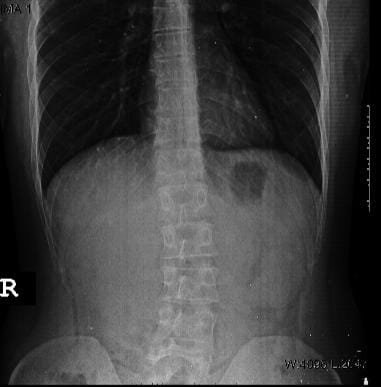

Arkadaşlar göz derecelerim bu şekilde (sph miyop cyl astigmat) bir de bel bölgesinde gördüğünüz gibi skolyoz var. Askeriye polislik için şansım nedir skolyozun derecesini tam bilemiyorum 15 i geçiyor sanırım ve göz için düşüncelerinizi merak ediyorum. Skolyoz ayakta çok uzun süre durunca sinir sıkışması yapabiliyor.

Skolyoz Hastasıyım